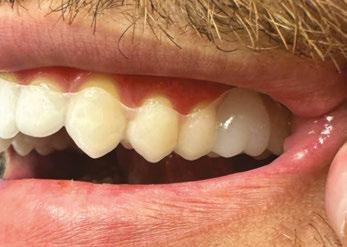

Clinical outcome

After 10 months, I’m pleased to report on the successful completion of Phase 1 treatment for the patient. His arches have

been expanded and aligned, and the space has been appropriately consolidated.

We successfully tipped the U2 roots mesially, which created a natural shield for the erupting U3s. As a result, the canines are now erupting naturally into a favorable path, avoiding root damage (Figure 5).

The patient and his mother are thrilled with the outcome, which exceeded their expectations and was achieved without emotional or physical distress. He now enjoys coming back to see us for his retainer checks because he had such a positive treatment experience.

Figure 5: JA final photos — 10 months total treatment time. Upper and lower arches expanded and aligned, anterior spacing consolidated, midlines centered, and U2 mesial root tip exaggerated